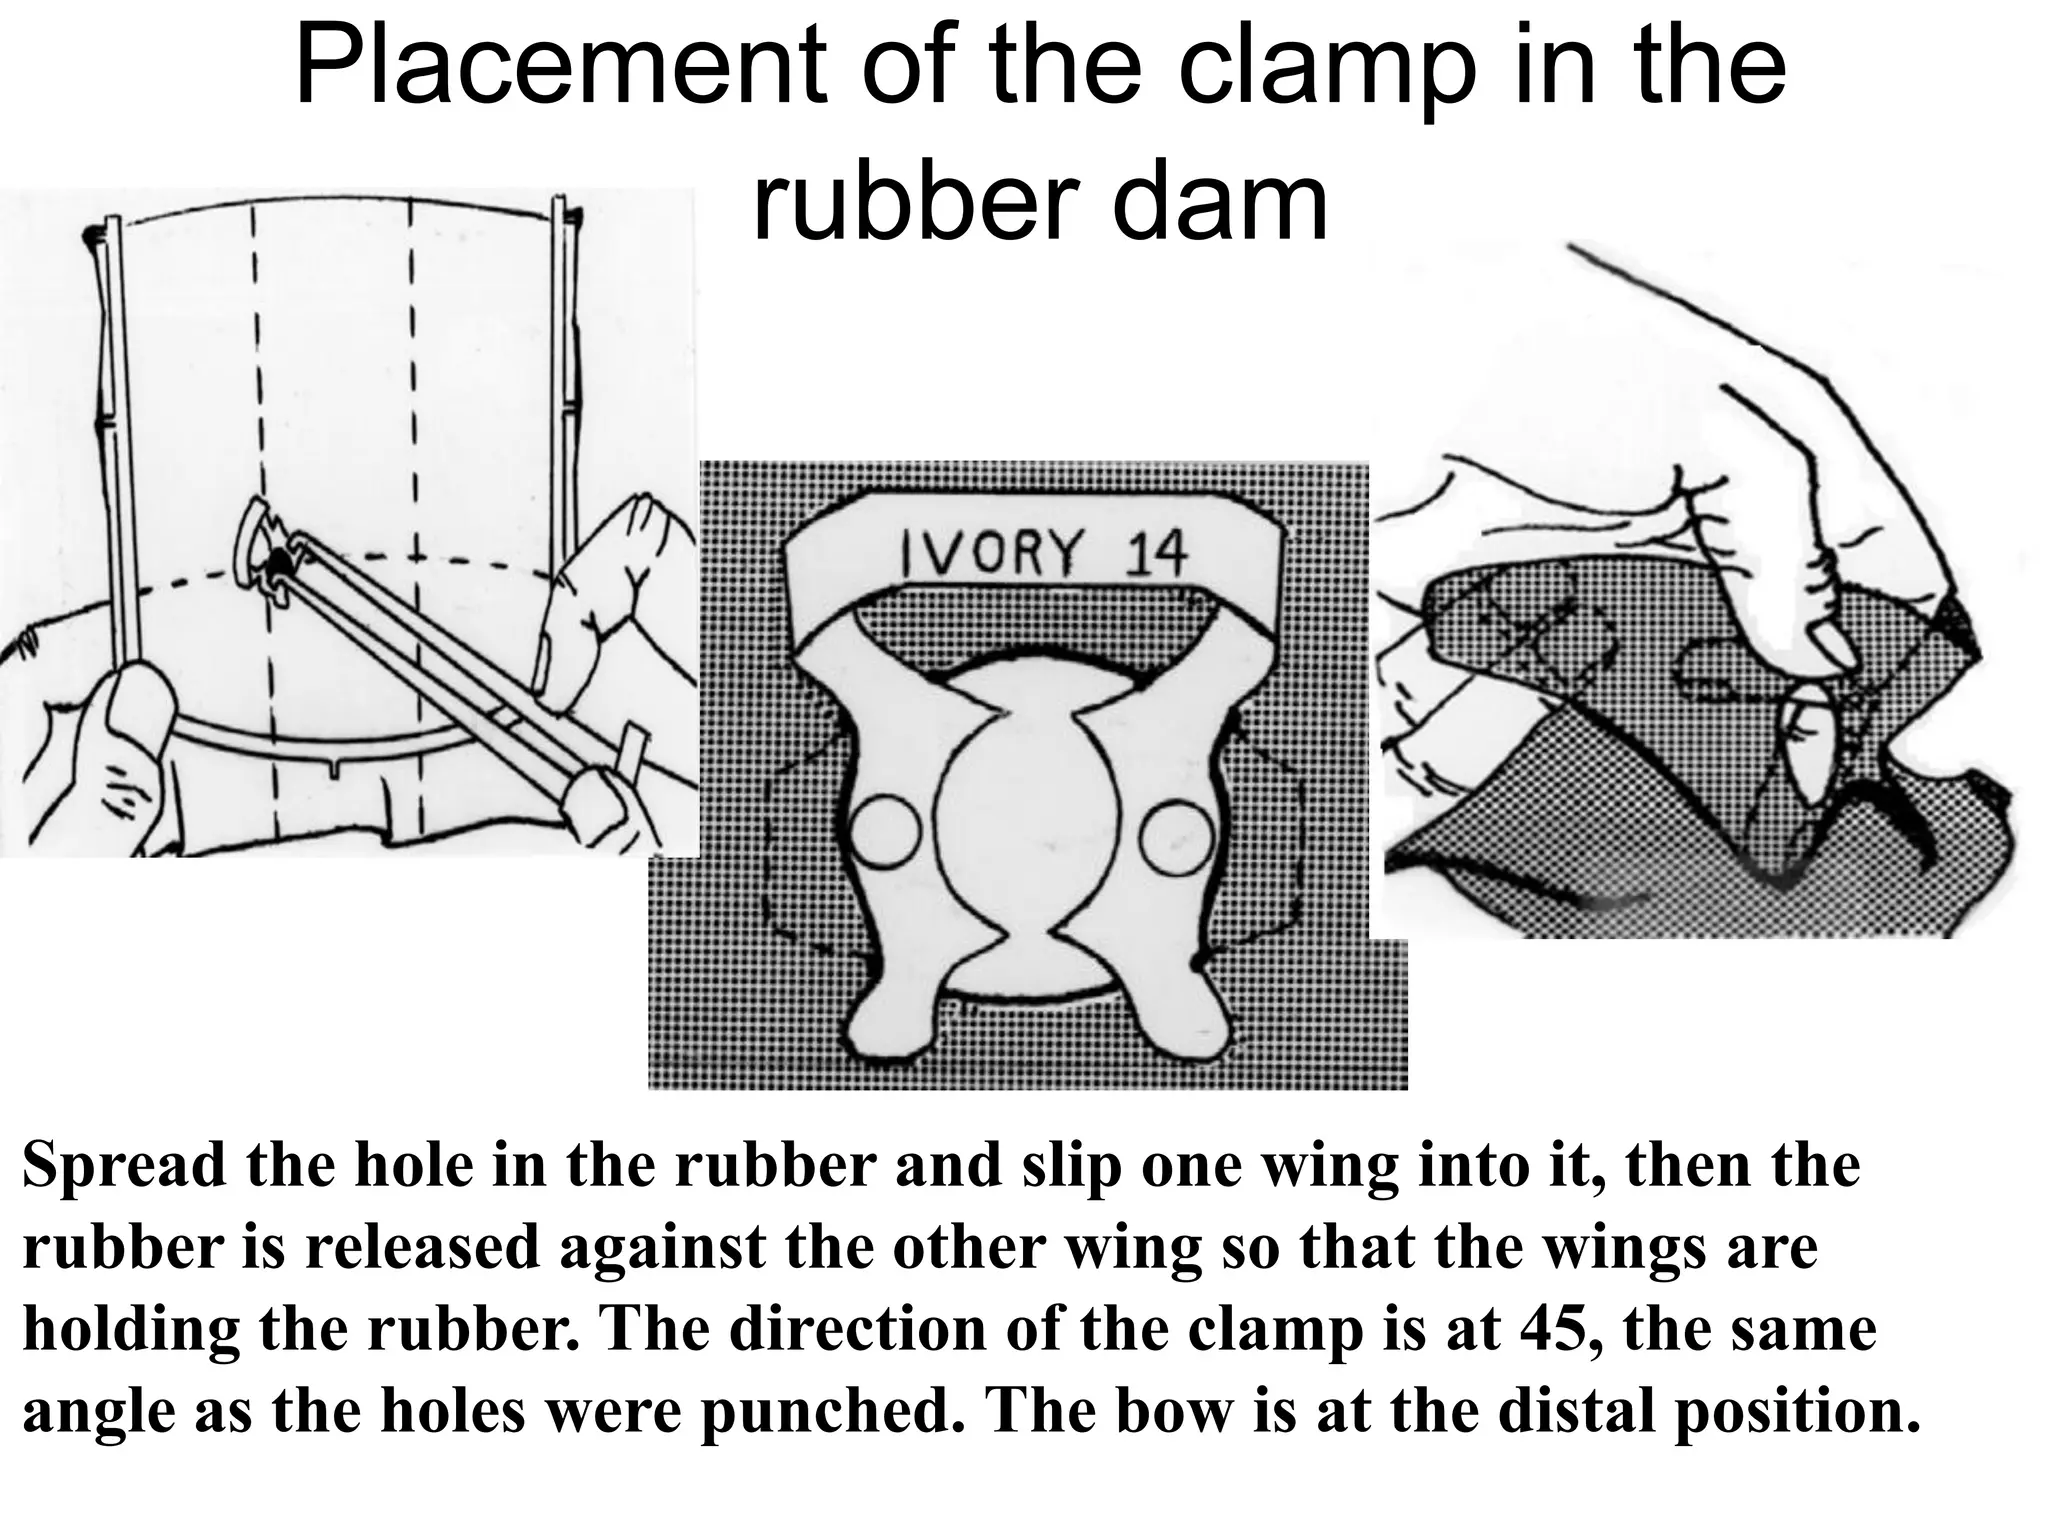

This document discusses the materials and components used for rubber dam isolation in dentistry. It describes the different types of rubber dam materials including color options and napkins to absorb moisture. It also outlines the tools needed such as punches to make holes, templates and stamps to guide hole placement, clamps to secure the dam, and other accessories like wedges and lubricant. Finally, it provides guidance on punching holes for different types of teeth and properly placing clamps in the rubber dam.